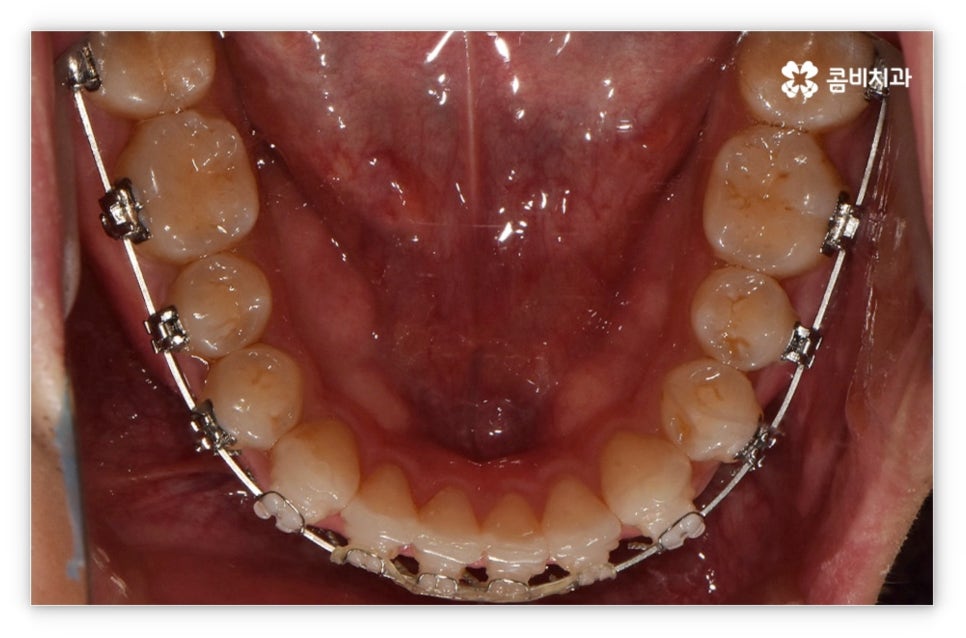

살펴본 바와 같이 앞니설측교정 의 장점에도 불구하고 아랫니 부분은 장치가 혀에 닿게 되기 때문에 환자분들께서 불편함을 느낄 수 있고 혹시라도 혀가 브라켓에 잘못 쓸리거나 눌렸을 때 통증이 발생할 수도 있으며 발음이 불분명해지는 문제가 생길 수 있는데요. 이러한 이유로 앞니설측교정 에 대해서 고민이 되시는 분들은 윗니 부분은 설측으로, 아랫니 부분은 일반 교정처럼 순측으로 진행하는 콤비 교정에 대해서 알아보시면 좋을 거예요. 위의 사진에서 살펴보실 수 있는 경우가 바로 이렇게 콤비 교정으로 진행한 환자분의 케이스인데 아랫니의 경우 보통 입술에 가려 별로 드러나지 않는 데다가 치아 색상인 세라믹 재질로 된 브라켓을 이용하기 때문에 설측 교정과 비교해도 심미성이 크게 떨어지지 않는다는 것을 알 수 있어요. 콤비 교정의 경우 설측 교정보다 비용적인 부담도 줄일 수 있으니 각 장치에 대한 장단점을 의료진분들과 충분히 상담하셔서 자신에게 맞는 장치를 선택하시면 좋을 거예요.